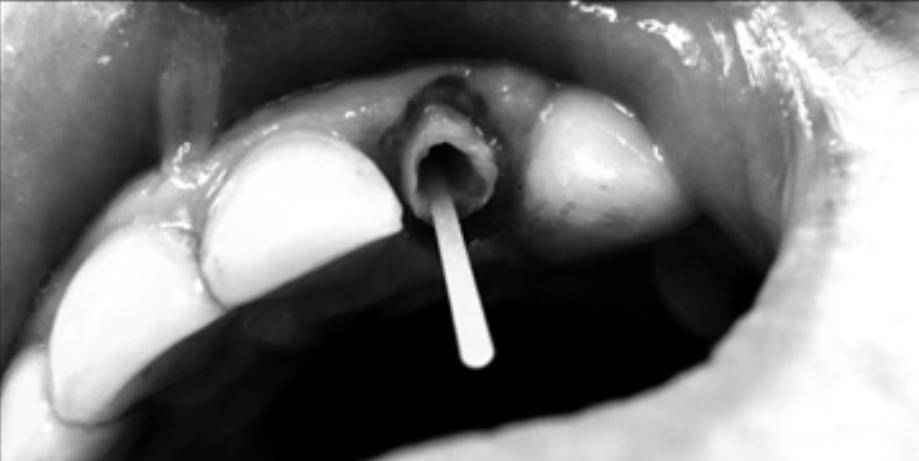

(Рис. 4).

Испаряем растворитель адгезивной системы в течении 5 сек и проводим полимеризацию (Рис. 5).

Получаем волоконный штифт с композитной обмазкой из прочного материала (Рис. 6).

Это позволит легко извлечь полученную полимерную вкладку, даже если в просвете корневого канала есть ретенционные элементы (Рис. 7).

Индивидуальный стекловолоконный штифт фото

Исходная ситуация. Просвет корневого канала несоответствует дизайну полимерного штифта

Изготовление индивидуального полимерного штифта